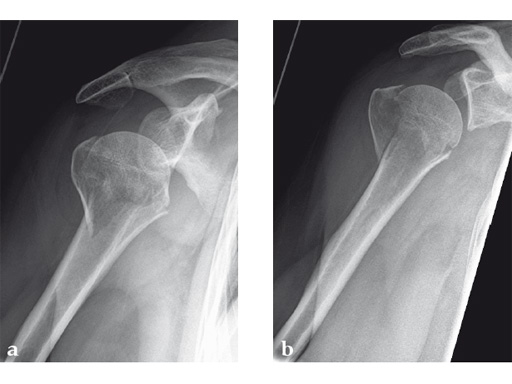

Case 2: Three-part valgus displaced fracture of the proximal humerus in a 63-year-old man.

The tuberosities have been reduced and fixed using intertubercular sutures (Fig 4). To reconstruct the medial support a calcar screw has been used. This determines the height of the nail. Therefore a 1 cm end cap has been used to get support for the proximal end of the nail in the part of the bone with the best bone quality.